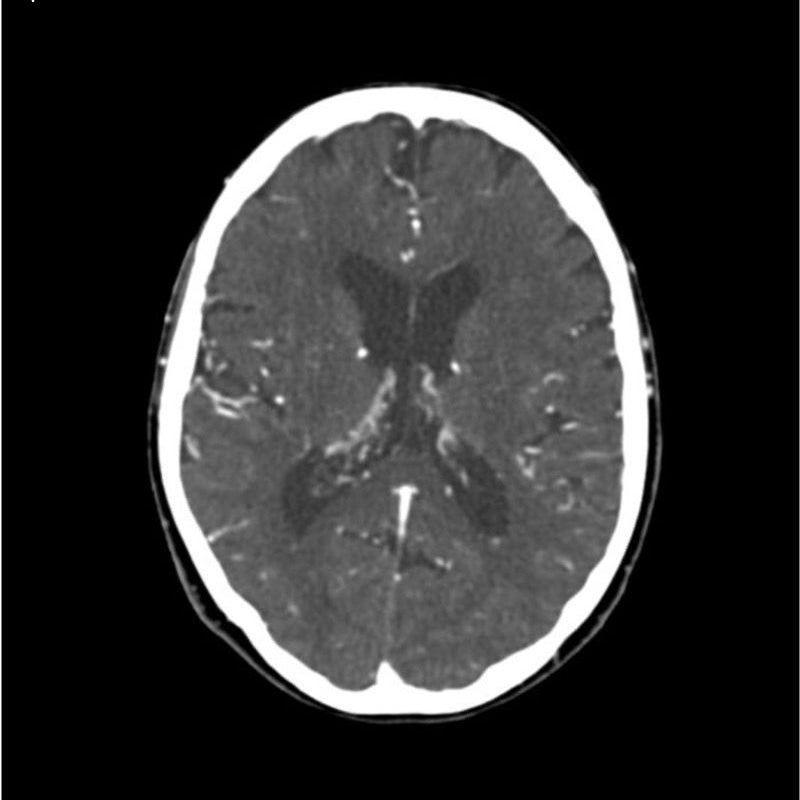

This phantom simulates a contrast medium enhanced head in arterial phase (CT angiography). The neck and upper thorax are included up to the aortic arch and the fifth thoracic vertebra. The vertex is included until approximately 0.5 cm below skin level. The thoracic phantom section excludes shoulder and back parts that are typically not part of CTA examinations. The interncal carotid artery has calcifications on both sides with moderate stenosis on the right side. Otherwise, the phantom has no significant vascular pathologies.

The phantom can be used in CT (including CBCT) to evaluate and optimize CTA imaging performance and post-processing applications such as vessel segmentation, including AI-enabled applications. It is also nicely suited for training purposes. The phantom provides a detailed and realistic simulation of vascular structures, soft and bone tissue, including small details such as lymph nodes. Air voids are filled with a cellulose-polymer composite of approx. -160 HU.

Realistic simulation of head and neck vessels up to the aortic arch, bone and soft tissues.

Calcifications of the internal carotid artery at the carotid bifurcation on both sides with mild stenosis on the right side.